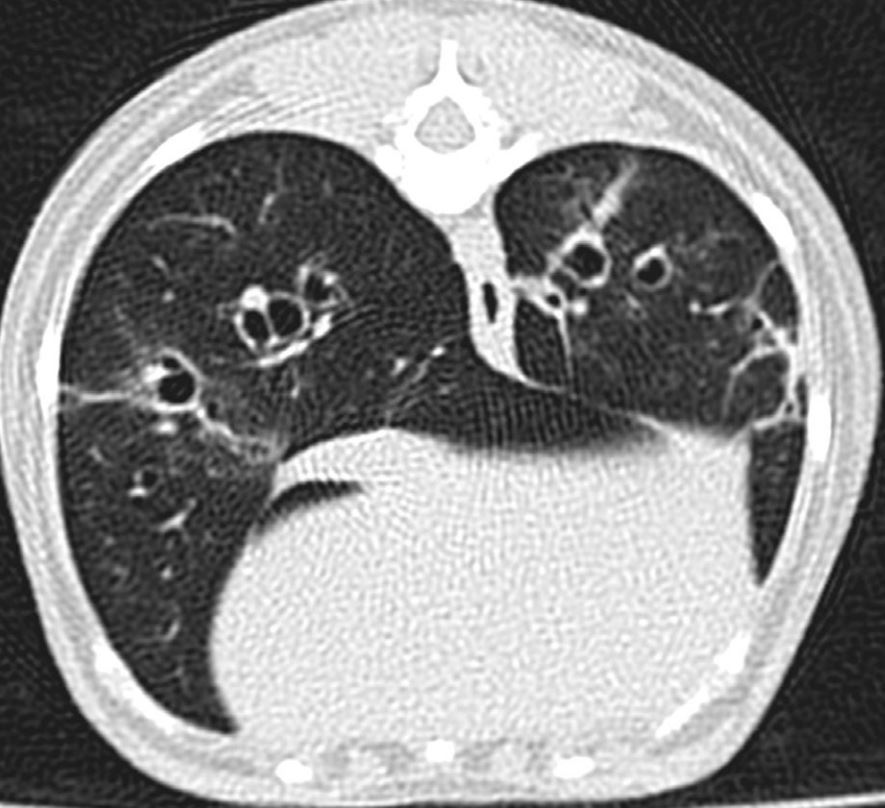

What is this representing?

A

Parenchymal bands - Fibrosis of the septa from chronic inflammation